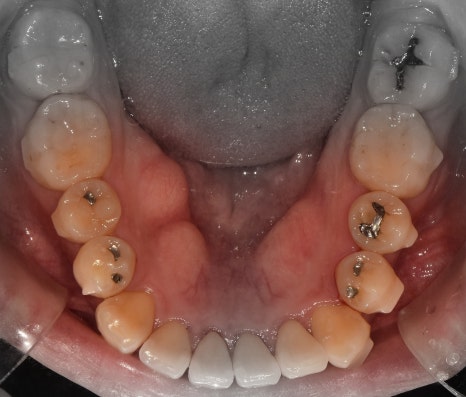

측면에서는 크게 2가지를 느낄 수 있습니다.

- 전치부 치아들의 치축, 전방 뻐드러짐

- 1치대 1치의 관계

*정상이라면, 1치대 2치의 관계를 가져야 됩니다.

또한, 측절치 및 송곳니의 총생들도 같이

관찰을 할 수 있습니다.

앞서, 1치대 1치 관계에 있던 교합관계들이

1치대 2치의 관계로 바뀐것을 볼 수 있으면서

길쭉하게 느껴졌던, U shape 형태의 악궁이

딱 보기 좋은, U shape 로 바뀌었죠.